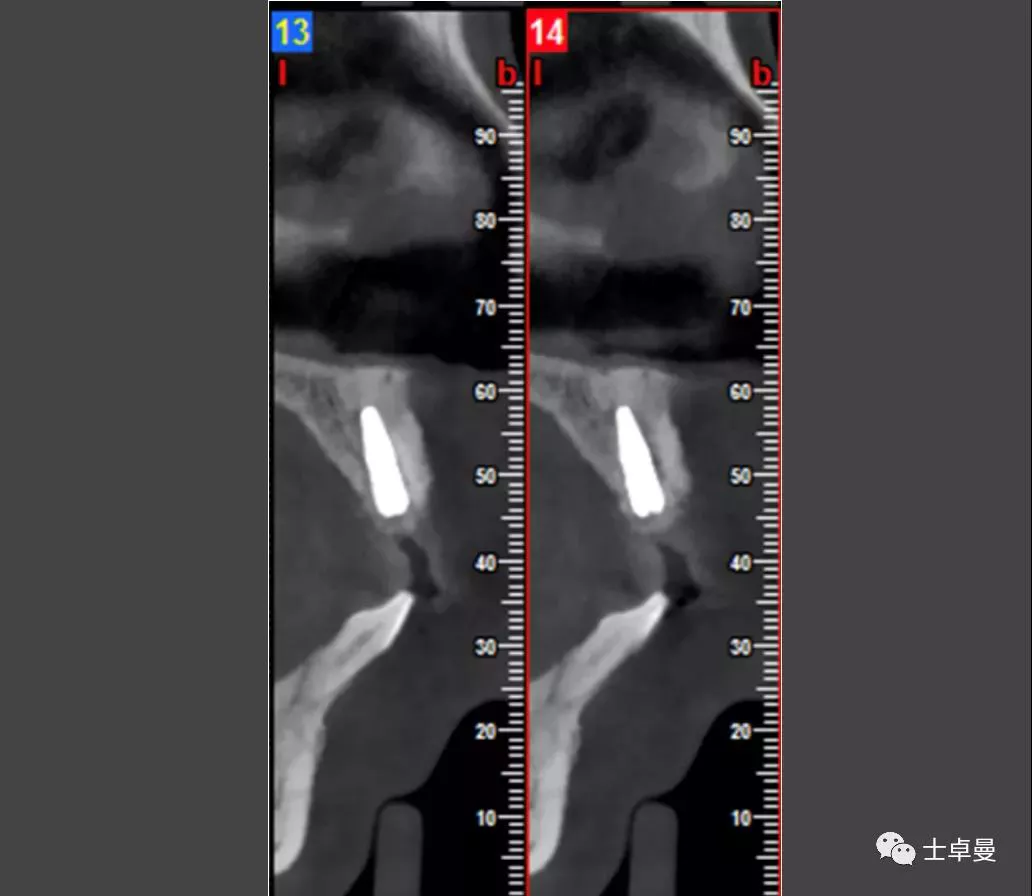

影像学检查

·      CBCT显示11可用骨高度13.3mm,宽度6.9mm;

·      12近中牙槽嵴吸收至根尖1/3处,远中牙槽嵴吸收至根1/2处;

·      21可见根吸收影相,近中牙槽嵴吸收至根尖1/3处;

·      22牙槽嵴近中吸收至根1/3处,远中吸收至根尖。